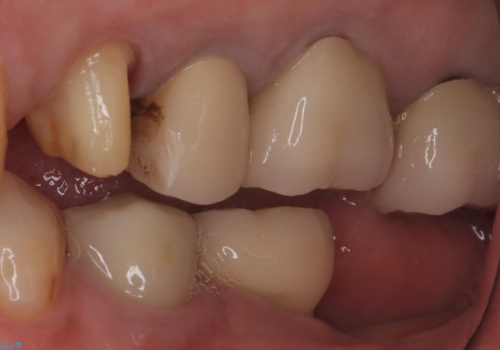

- 主訴:昔入れた被せものの境目の黒いところが気になる

クラウンの不適により境目に汚れが溜まり、黒く見えていました。

適合の良いクラウンへやり替えることとしました。

古いクラウンを除去し、不適部位から中で広がっていたカリエスを除去したのちCRにて築造、仮歯を経てセラミッククラウンをセットしています。